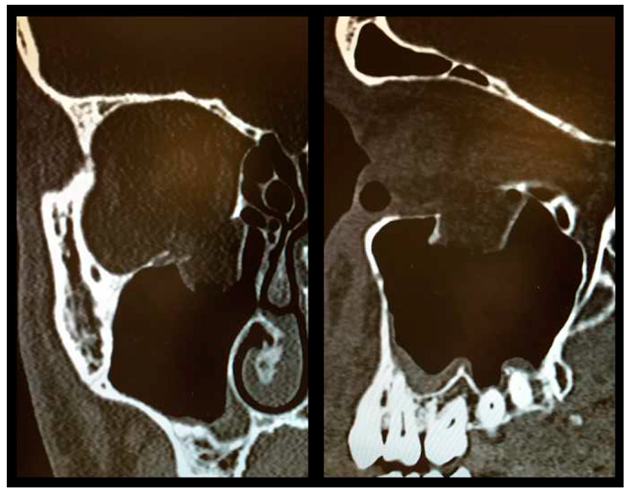

Figure 3.

Postoperative CT scan following OFF reduction and placement of Ethisorb® ((left) coronal view, (right) sagittal view).